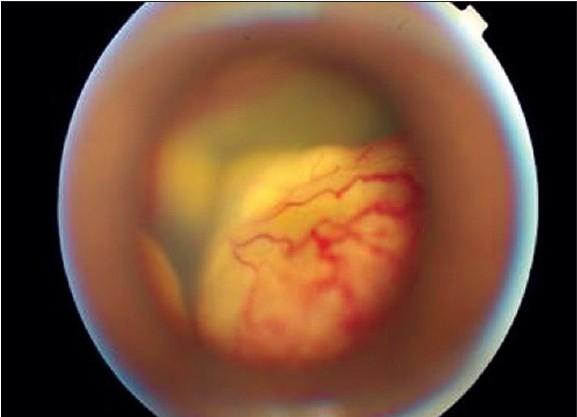

We describe the role of intravitreal anti-vascular endothelial growth factor (VEGF) agents in Coats' disease in children. In a prospective, interventional, non-randomized case series, three patients (three eyes) aged 16, seven and two years were diagnosed to have Coats' disease. In Case 1 (16 yr/ male) with macular edema, previous laser photocoagulation being unsuccessful, intravitreal pegaptanib sodium (Macugen) was tried. Case 2 (seven yr/ male) and Case 3 (two yr/ female) were diagnosed to have Stage 4 Coats' and underwent external needle drainage, laser photocoagulation, SF6 gas injection and intravitreal injection of bevacizumab (Avastin). Reduction of exudation and attached posterior pole (Cases 2 and 3) was seen at a follow-up of six months and two months respectively. Intravitreal anti-VEGF agents may be successfully used as adjunct treatment in select cases of Coats' disease in childhood.

我们描述了眼内抗血管内皮生长因子(VEGF)药物在儿童 Coats 病中的作用。在一项前瞻性、干预性、非随机病例系列研究中,我们诊断出 3 名(3 只眼)年龄为 16 岁、7 岁和 2 岁的儿童患有 Coats 病。在患有黄斑水肿的病例 1(16 岁/男性)中,先前的激光光凝治疗不成功,尝试了眼内注射帕珠单抗钠(Macugen)。病例 2(7 岁/男性)和病例 3(2 岁/女性)被诊断为 4 期 Coats 病,并进行了外路针拨术、激光光凝、SF6 气体注射和眼内注射贝伐单抗(Avastin)。在 6 个月和 2 个月的随访中,分别观察到渗出物和后极附着的减少(病例 2 和 3)。眼内抗 VEGF 药物可作为儿童 Coats 病的一种辅助治疗方法,在一些选择病例中可能取得成功。